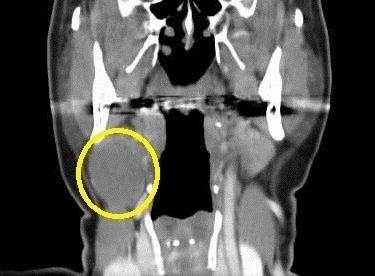

아가미라고도 불리는 새열은 태아기에 목이 만들어질 때 있다가 없어지는 것이 정상적이나, 그렇지 않아 생기는 증상인 것이다. 아가미 틈새가 닫히지 않고 태어나 이 부분이 결국 물혹 형태의 새열낭종, 구멍 형태의 새열로 등으로 나타나는데 나는 이 중 새열낭종에 해당하게 된 것이다.

새열낭종도 1형과 2형으로 나누어지는데 1형은 귀 부근에 증상이 나타나고, 2형은 목 부근에 증상이 나타난다고 한다. 나는 2형에 해당했고 가장 흔한 증상이라고 한다.

새열낭종 진단 사진 (출처 : 땡큐서울의원 https://thanqseoul.modoo.at/?link=6ffedydb)